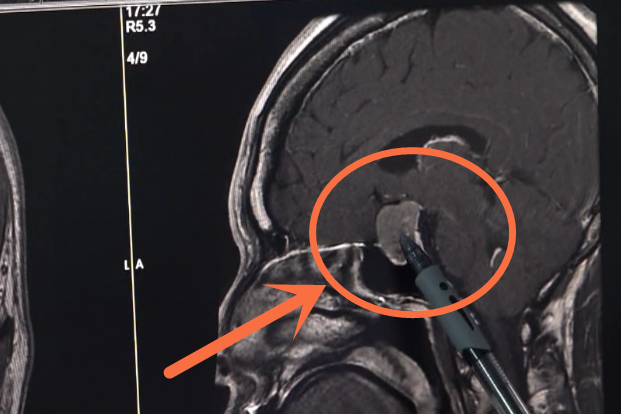

家住在江门的王红(化名)今年48岁,3月底的时候一向身体健康的她突发头痛呕吐,当地医院在她的脑中发现了脓肿,但保守治疗半个月后王红的症状不但没有好转,还逐渐加重:“人从一开始清醒,到后面精神变差。”

据家属介绍,王红在两三岁的时候右耳就曾因中耳炎而导致鼓囊穿孔,去年6月份,中耳炎又复发了当时用消炎药和滴耳液治疗后症状有好转便没有太在意,没想到,会导致这么严重的后果。

医院专家表示王女士的脑部脓肿是由中耳炎引起的,来医院检查后发现脓肿不断增加,水肿明显加重,可随时造成颅内大面积感染甚至危及生命。

中耳位置距颅内较近,与颅内只有骨板一“纸”之隔,所以炎症很容易突破骨板进入脑内,引发大脑颞叶脓肿和小脑脓肿等威胁到生命的并发症。